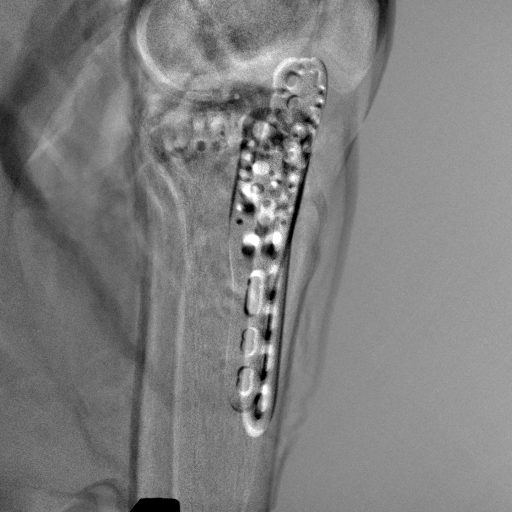

5.4 Real Knee Data with Metal Implants

Refer to caption

Figure 13: Three examples of synthetic perspective projection images for training, intensity window: [0, 4]. The appearance (e.g., image contrast and metal image resolution) of such DRR training images is different from that of real projection images in Fig. 14.

0superscript00^{\circ} perspective

Pix2pixGAN

TransU-Net

Figure 14: The results for the real cadaver leg data. The green dots mark the positions of landmarks in the corresponding reference images. In the first column, the arrows indicate the bone cavity/fracture structures. In the second column, the solid lines mark the widths and heights of the metals. The green ones are measured from the DRR reference, while the red ones are measured in the corresponding perspective projection image. In the last column, the lines mark the centerlines of the metal screws, where the green lines are those from the reference image. The lengths of the lines in mm are displayed in their corresponding subcaptions. Intensity window: [0, 4]. Please zoom in for better visualization.

The complementary view setting for learning perspective deformation is also evaluated on real CBCT projection data. In this evaluation, real CBCT projection data from a dataset of knees with metal implants is used for testing, while DRRs created from volumetric CT datasets with inserted metals is used for training. Three exemplary DRR perspective projection images for training are displayed in Fig. 13, in which synthetic metal implants are inserted [34]. The appearance, e.g., image contrast and metal image resolution, of such DRR training images is different from that of real projection images in Fig. 14. In Fig. 14, the results for three knees, with and without metal implants, are displayed. The first and second rows are the 0superscript00^{\circ} and 180superscript180180^{\circ} perspective projections, respectively, rebinned to the virtual detector with geometric calibration based on their respective principal points and projections of the world origin. The third row displays their difference images, where the magnitude of deviation increases from the center towards the outside like it does in DRRs with an ideal scan trajectory (e.g., Fig. 6(e)), although real projection data suffer from various physical effects like beam hardening and Poisson noise. The fourth row displays the RGB stacks of 0superscript00^{\circ} and 180superscript180180^{\circ} perspective projection images. The magenta and green regions indicate structures with considerable perspective deformation, for example, the knee patella in Fig. 5.4, the top parts of the two metals in Fig. 5.4, and the bottom two screws in Fig. 5.4. The fifth row displays reference images, which are orthogonal projections of iterative reconstruction volumes from measured CBCT projection data. In the reference images, a total of five landmarks are selected, with the positions being marked by the green dots: In Fig. 5.4, two positions at the edges of the knee patella are marked; In Fig. 14(e) and Fig. 14(f), one position at the left edge of the fibula is marked for each image. In addition, a rectangular frame for the two metals is marked by the green dashed lines, while its width and height are indicated by the green solid lines, which are 29.71 mm and 111.99 mm, respectively. In Fig. 14(f), the centerlines of the bottom two screws are sketched by the green lines, which have the lengths of 17.14 mm (middle screw) and 19.38 mm (bottom screw). The corresponding rectangular frame for the two metals and the screw centerlines in the perspective projection images are marked as well, but in red color. In Fig. 14(a), the width and height of the metals are 32.56 mm and 109.85 mm, which have deviations of 2.84 mm and -1.95 mm to the reference ones, respectively. In Fig. 14(b), the centerline lengths are 18.91 mm and 19.54 mm, which have deviations of 1.77 mm and 0.16 mm, respectively. Although the bottom screw has little length deviation to the reference, the orientations of both screws are obviously deviated. The sixth row shows the results of Pix2pixGAN using 0superscript00^{\circ} and 180superscript180180^{\circ} polar inputs. For all of the landmarks, the green reference dots are all located accurately in the Pix2pixGAN images. The rectangular reference frame also accurately covers the metals in Fig. 14(g). In Fig. 14(h), although the two red centerlines do not exactly overlap with the green one, they are very close in lengths and orientations. Please zoom in for better visualization.

(a) Real 0superscript00^{\circ} perspective

(b) DRR reference

(c) Pix2pixGAN

Figure 15: The enlarged ROIs containing the cavity structures to demonstrate differences in image resolution.

The region-of-interest covering the cavity/fracture structures indicated by the red arrow in Fig. 14 has been enlarged in Fig. 15 for better visualization of image resolution. In the real 0superscript00^{\circ} perspective projection ROI (Fig. 15(a)), the cavities and bone edges appear sharp. The presence of Poisson noise can also be visualized to some degree. In the DRR reference ROI (Fig. 15(b)), the cavities and bone edges appear blurry. This is likely caused by the partial volume effect in the intermediate 3D reconstruction volumes. In the Pix2pixGAN output (Fig. 15(c)), there is a slight smoothing effect. For example, the fine edge indicated by the arrow is blurred and the Poisson noise is reduced. But in general, image resolution is preserved for most anatomical structures, e.g., the cavities.